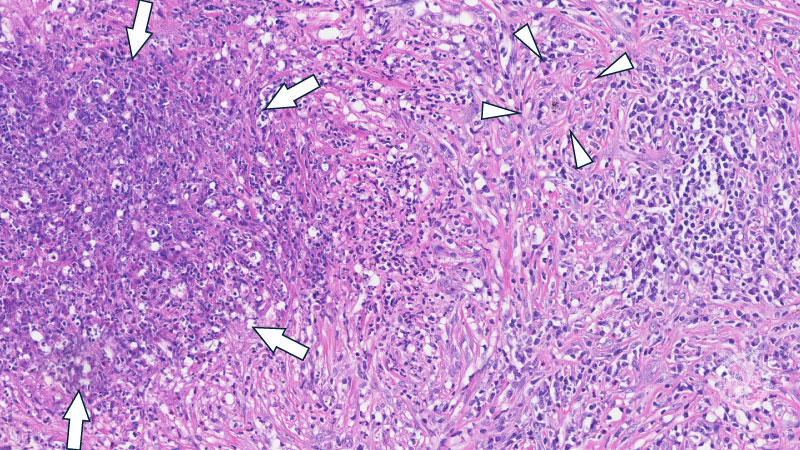

ミクロ像 (HE中拡大): 著明な好中球浸潤を伴う壊死部(矢印)とそれを取り囲む肉芽腫性病変。HE染色では巻き込まれた血管(矢頭)と血管炎は判別が難しい。